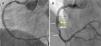

A 67-year-old man with hyperlipidemia was admitted for effort angina. Fifteen years before he had suffered an anterior myocardial infarction and a bare-metal stent (BMS) was implanted in the proximal left anterior descending coronary artery. Coronary angiography revealed proliferative ISR involving the proximal segments of the BMS but also extending 10 mm into the proximal vessel. OCT depicted severe neoatherosclerosis, with heavily calcified plaques, and a thin-cap fibroatheroma in the proximal segment. After aggressive lesion predilation the entire segment was covered with a 3.5 mm×23 mm BVS (Absorb, Abbott Vascular, CA), postdilated using a non-compliant balloon up to 24 atm, with an excellent final result (Figure 3A and B). OCT confirmed correct BVS expansion with a small residual coronary dissection behind the BVS and at its proximal border. The patient remained completely asymptomatic but a scheduled control angiogram at nine months revealed the development of a large CAA in the mid portion of the BVS (Figure 3C and D). OCT provided unique additional insights, revealing a CAA 11 mm in length with a maximum lumen area of 27.5 mm2. Notably, a striking displacement of the BVS struts was depicted, confirming the occurrence of BVS fracture (Figure 4).

(A-D) Optical coherence tomography images of the coronary artery aneurysm (CAA) (yellow arrow) with a maximum lumen area of 27.5 mm2. Some struts of the bioresorbable vascular scaffold appear covered but largely malapposed (A, thin yellow arrow), others were extensively displaced (B), whereas no struts could be detected in other areas of the CAA (C); (D) longitudinal view. * denotes wire artefact. LA: lumen area.